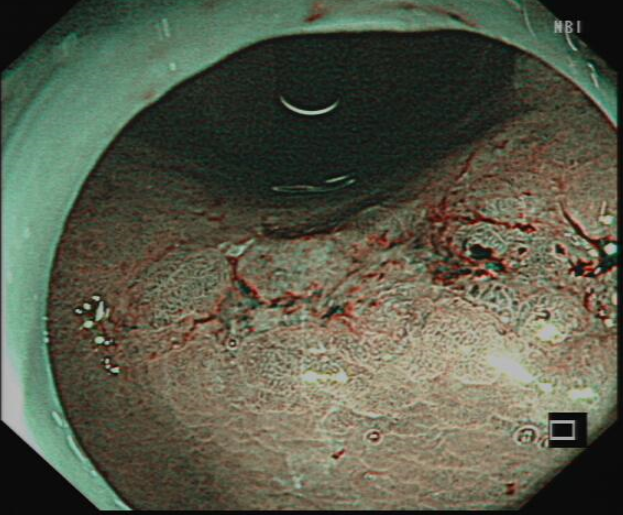

图2胃镜:NBI下病变表现

ESD术前进行内镜精查发现病变胃镜白光下,NBI放大观察及靛胭脂染色,病变均符合内镜下胃早癌表现。胃角病变是ESD操作最困难部位,随着充气的增多,镜身会远离胃角,不容易接近病变,增加了剥离难度,术中又发现病变中央存在纤维化粘连,为手术剥离增加了风险,唐印华教授凭借精湛的技术和丰富的腔镜经验,利用牙线—钛夹牵引,增加了黏膜下层的空间,使黏膜下视野充分暴露,且镜身更容易接近病变,大大提高了剥离的速度,使手术快速顺利结束。